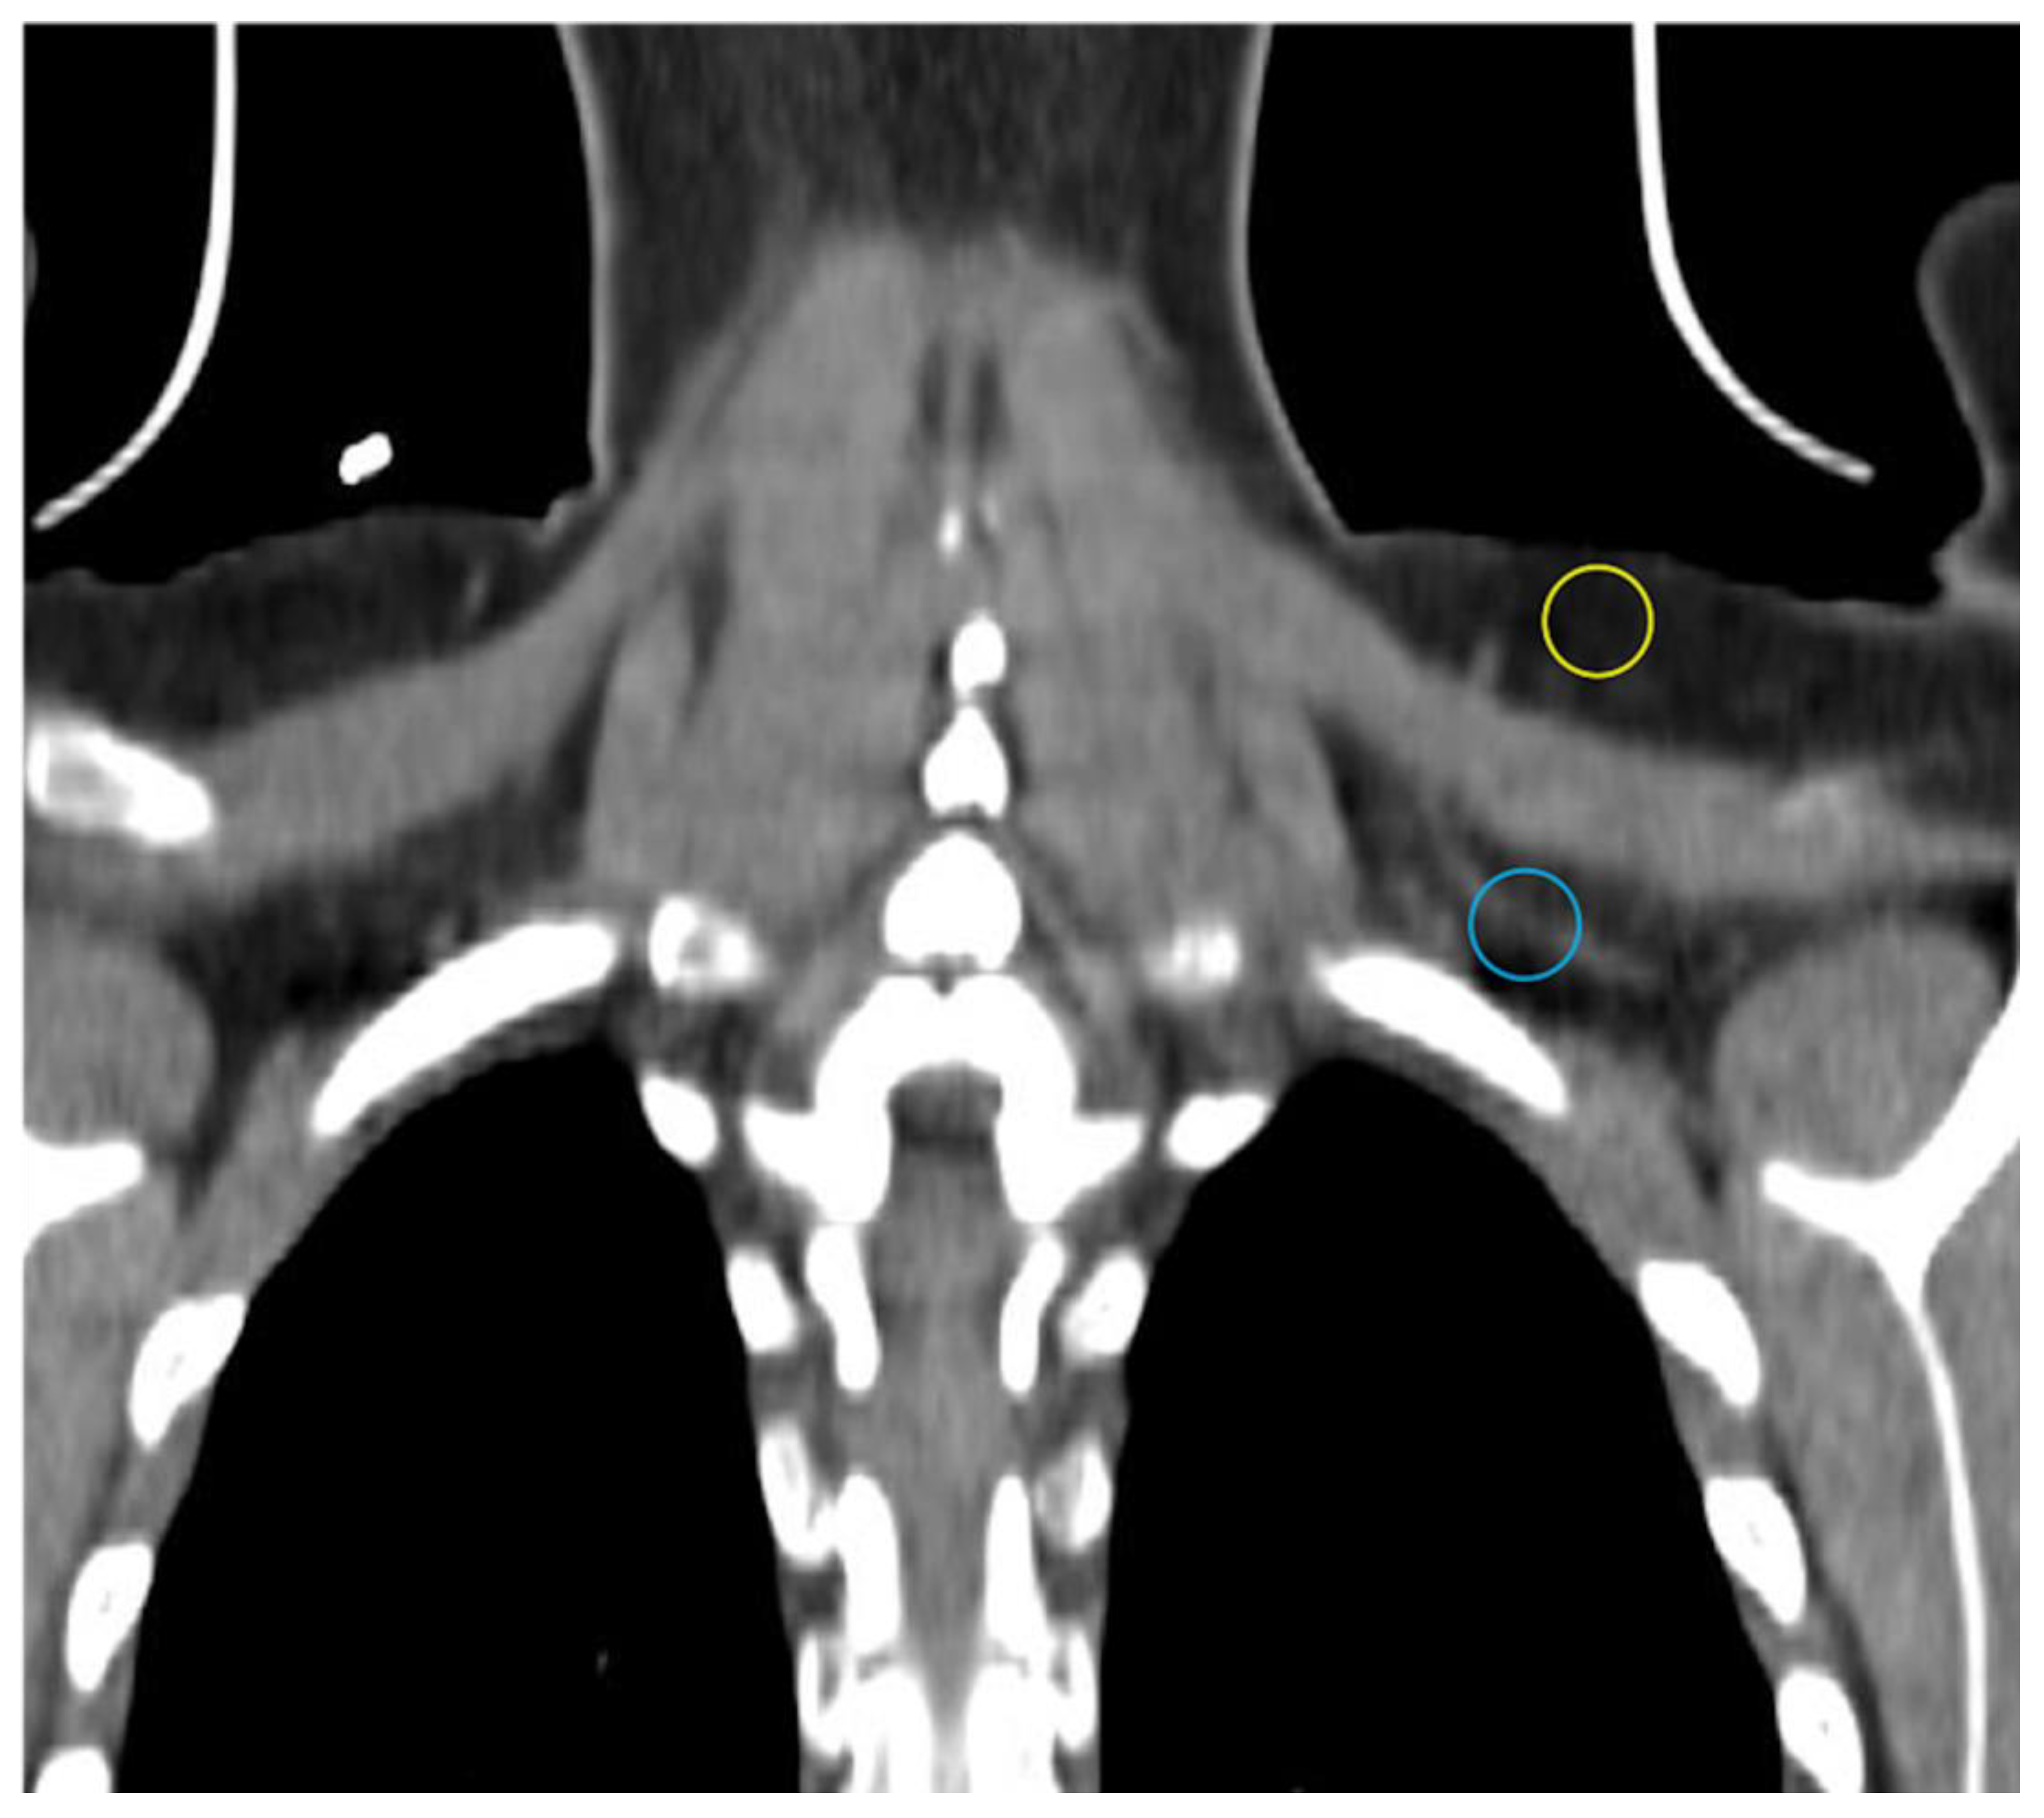

Stojanovska and colleagues showed water-fat imaging distinguishes ex vivo samples of BAT, WAT, and mixed BAT/WAT from each other. Specifically, the proton density fat fraction as a percent was significantly lower in BAT compared to other samples [34]. As mentioned above, this is because BAT has less lipid deposits than WAT. A similar technique successfully discriminated BAT from WAT in rodents and additionally correlated the two different depots with specific CT HU ranges [35]. Dixon-based MRI, a technique for generating fat and water images, and several investigational water-fat algorithms have differentiated iBAT from WAT in human subjects [19,36,37,38,39]. Results were confirmed by FDG uptake detected separately on PET/CT or in the same scan via PET/MRI [19,38,40]. At thermoneutral conditions, the MR fat fraction differentiates iBAT from WAT with greater sensitivity than FDG-PET/CT (Figure 3) [19,41,42]. Cold stimulation accentuates the fat-fraction difference between BAT and WAT, as even short-duration cold exposure induces lipid utilization by Ucp1-rich adipocytes [20,39,40]. A limitation of fat-fraction MR in this setting is variability between subjects in the optimal cutoff value to distinguish BAT from WAT [21]. Romu and colleagues showed calibrating fat images based on the T2*-derived fat content of WAT to form relative fat content images can identify BAT in rats and may avoid the pitfall of inter-subject variability by using an internal control [35].

Figure 3.

MRI vs. FDG-PET/CT in detection of BAT. FDG-PET/CT and MRI of a healthy BAT-positive research subject. FDG uptake is visible in supraclavicular BAT with cold exposure on the PET maximum intensity projection (MIP; E, red arrows) and absent from the thermoneutral PET MIP (A). CT shows adipose tissue in the same region (B,F) and PET shows increased standardized uptake value there after exposure to cold (C,G). MRI-derived fat signal fraction from the same subject shows adipose tissue with relatively low levels of fat (white ovals) in the same region at thermoneutral and cold conditions (D,H). Image reproduced with permission from reference 41.